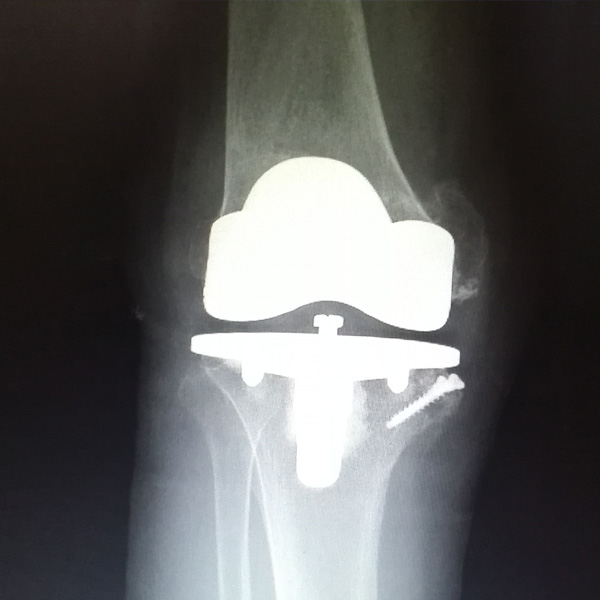

膝關節(jié)內(nèi)翻

患者劉某某,女66歲,左側膝關節(jié)嚴重內(nèi)翻(俗稱的“羅圈腿”),疼痛到不能生活自理。經(jīng)平臺推薦到哈爾濱醫(yī)科大學附屬第二醫(yī)院骨關節(jié)科就診,......